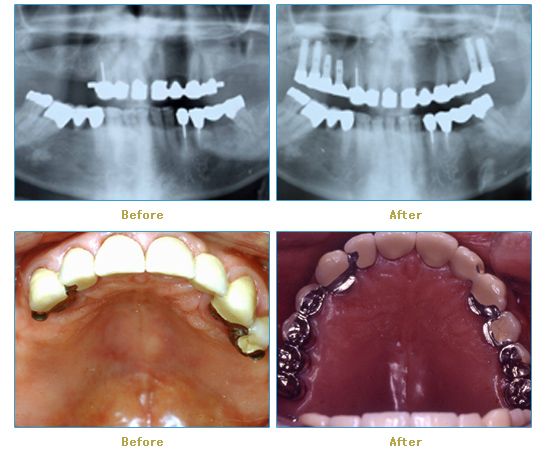

Dr. Cabianca has restored hundreds of smiles through the latest techniques in restorative and cosmetic dentistry. The following before and after photos document a few such cases in which Dr. Cabianca has replaced and reshaped teeth to produce wonderful smiles. Click on any of the images below to view larger versions of the photos.